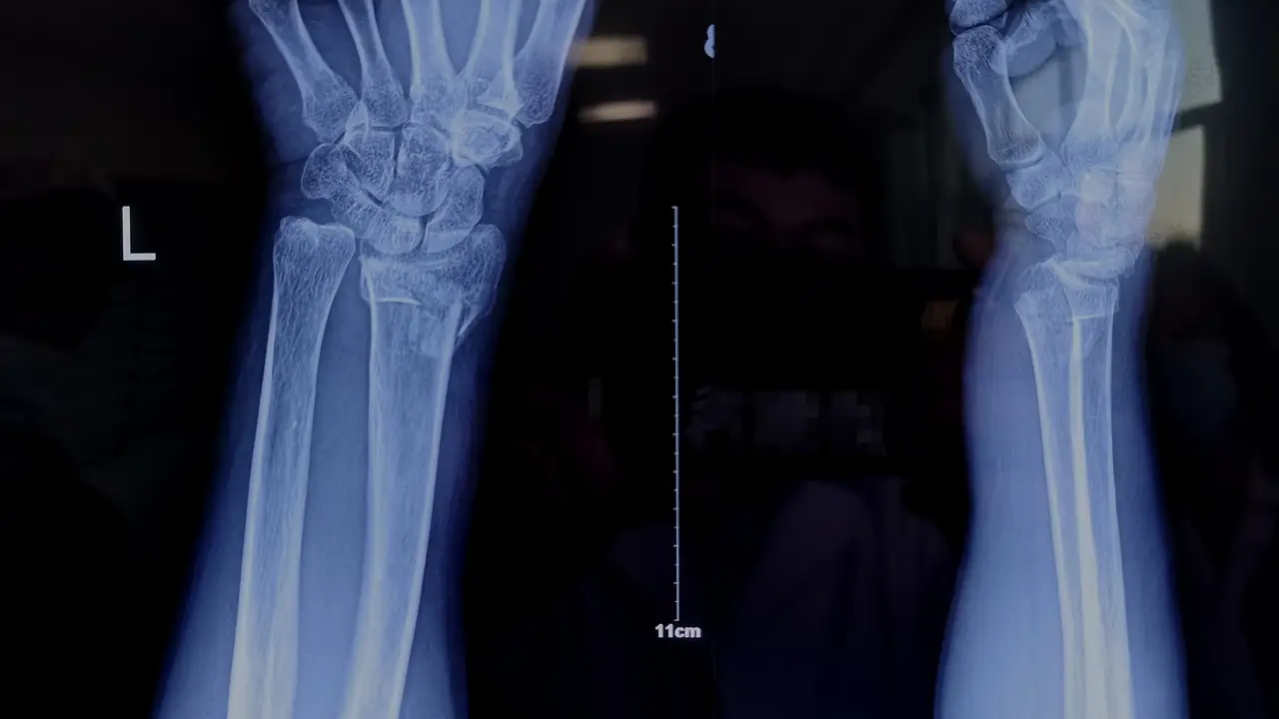

临床工作中,对于骨折的治疗,许多时候我们常常采取保守治疗,保守治疗的方法为予以骨折断端手法复位并妥善固定,常见的固定方式有石膏、夹板、支具等等。

对于骨折保守治疗期间有时也会遇到骨折再移位情况。尤其是骨折复位1-2周后复查发现原本复位良好的骨折断端移位了,这时常常建议病人手术固定,偶尔能听到患者不解的质疑声音:

对于骨折再次移位能给的说法只有一个,就是骨折断端手法复位后出现再次移位是骨折保守治疗过程中出现的、且无法避免的一种现象,就像吃药就可能面临不良反应一样。

多数移位发生在复位后2周内,其原因是由于肢体肿胀逐渐消退,出现石膏松动,在肢体活动、肌肉收缩牵拉等因素导致骨折断端逐渐发生移位,尤其是不稳定骨折!用木棍做一个比喻,横行截断,较容易维持断端稳定,斜行截断,断端容易移位,不容易维持稳定!

- 不稳定性骨折:斜形骨折、螺旋骨折、粉碎性骨折等。( 手法复位后容易发生骨折再移位! )

对于不稳定骨折,保守治疗发生再移位几率高,复位后定期复查X线片,若出现明显移位,通常建议手术治疗,从而使骨折端更好的复位及维持断端稳定,促进肢体功能恢复。